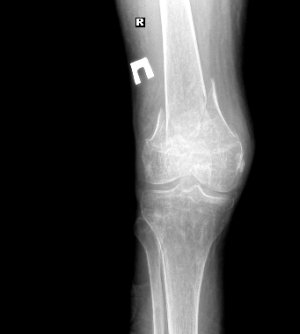

Случился "вколоченный осколочный, косой внесуставной перелом нижней трети диафиза правой бедр. кости с незначительным заходом осколков без признаков консолидации" а так 1.jpg2.jpgже "осколочный внутрисуставной перелом основы правого надколенника без смещения, без признаков консолидации"(снимки

http://fastpic.ru/view/59/2013/1022/81096fc26fcb57d606ecc6ce5a2f254d.jpg.html). Врачи в связи с тем, что у меня нижняя параплегия ограничились наложением лангеты на коленный сустав часть голени и часть бедра. Интересует следующее: как повлияет укорочение ноги в связи с этим переломом на процесс реабилитации и вероятного прямохождения (надеюсь что буду ходить), насколько она станет короче (можно ли судить по снимкам) и каковы есть решения проблемы неравности ног? Насколько целесообразно делать операцию и укреплять перелом пластинами и т.д. в моем положении на фоне остеопороза?